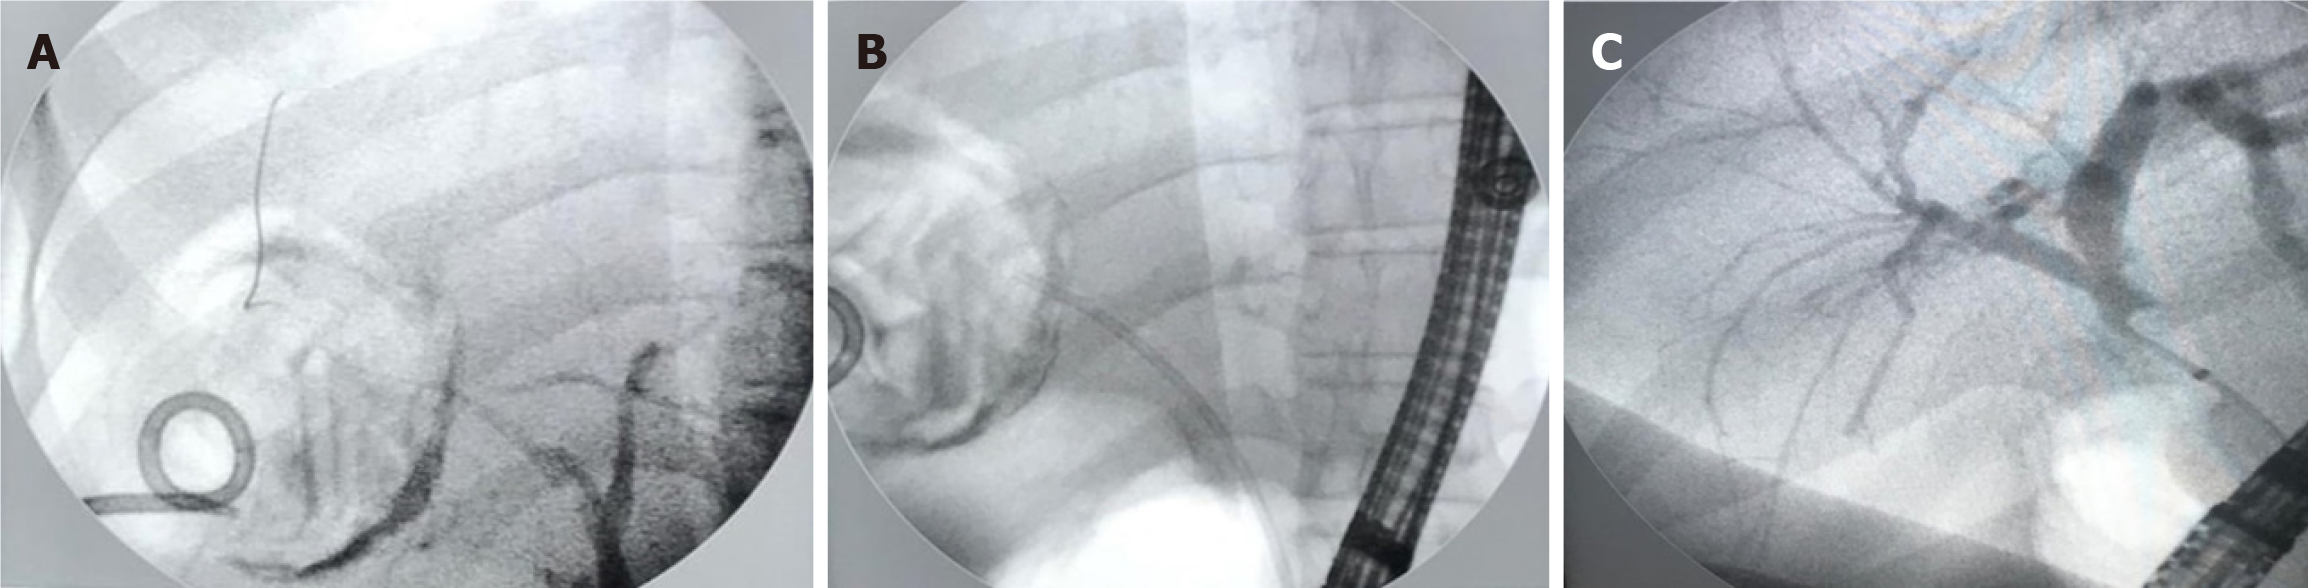

Figure 2 Endoscopic retrograde cholangiopancreatography of 20-year-old female who developed biliary fistula following hepatic hydatid cyst-related intervention.

A: Cholangiogram shows contrast extravasation from the right intrahepatic duct in a 20-year-old female patient following hepatic hydatid cyst related intervention; B: Sequential pictures show 7 Fr 12 cm biliary stent placement; C: Follow-up endoscopic retrograde cholangiopancreatography shows clearly visible right bile duct and its branches.